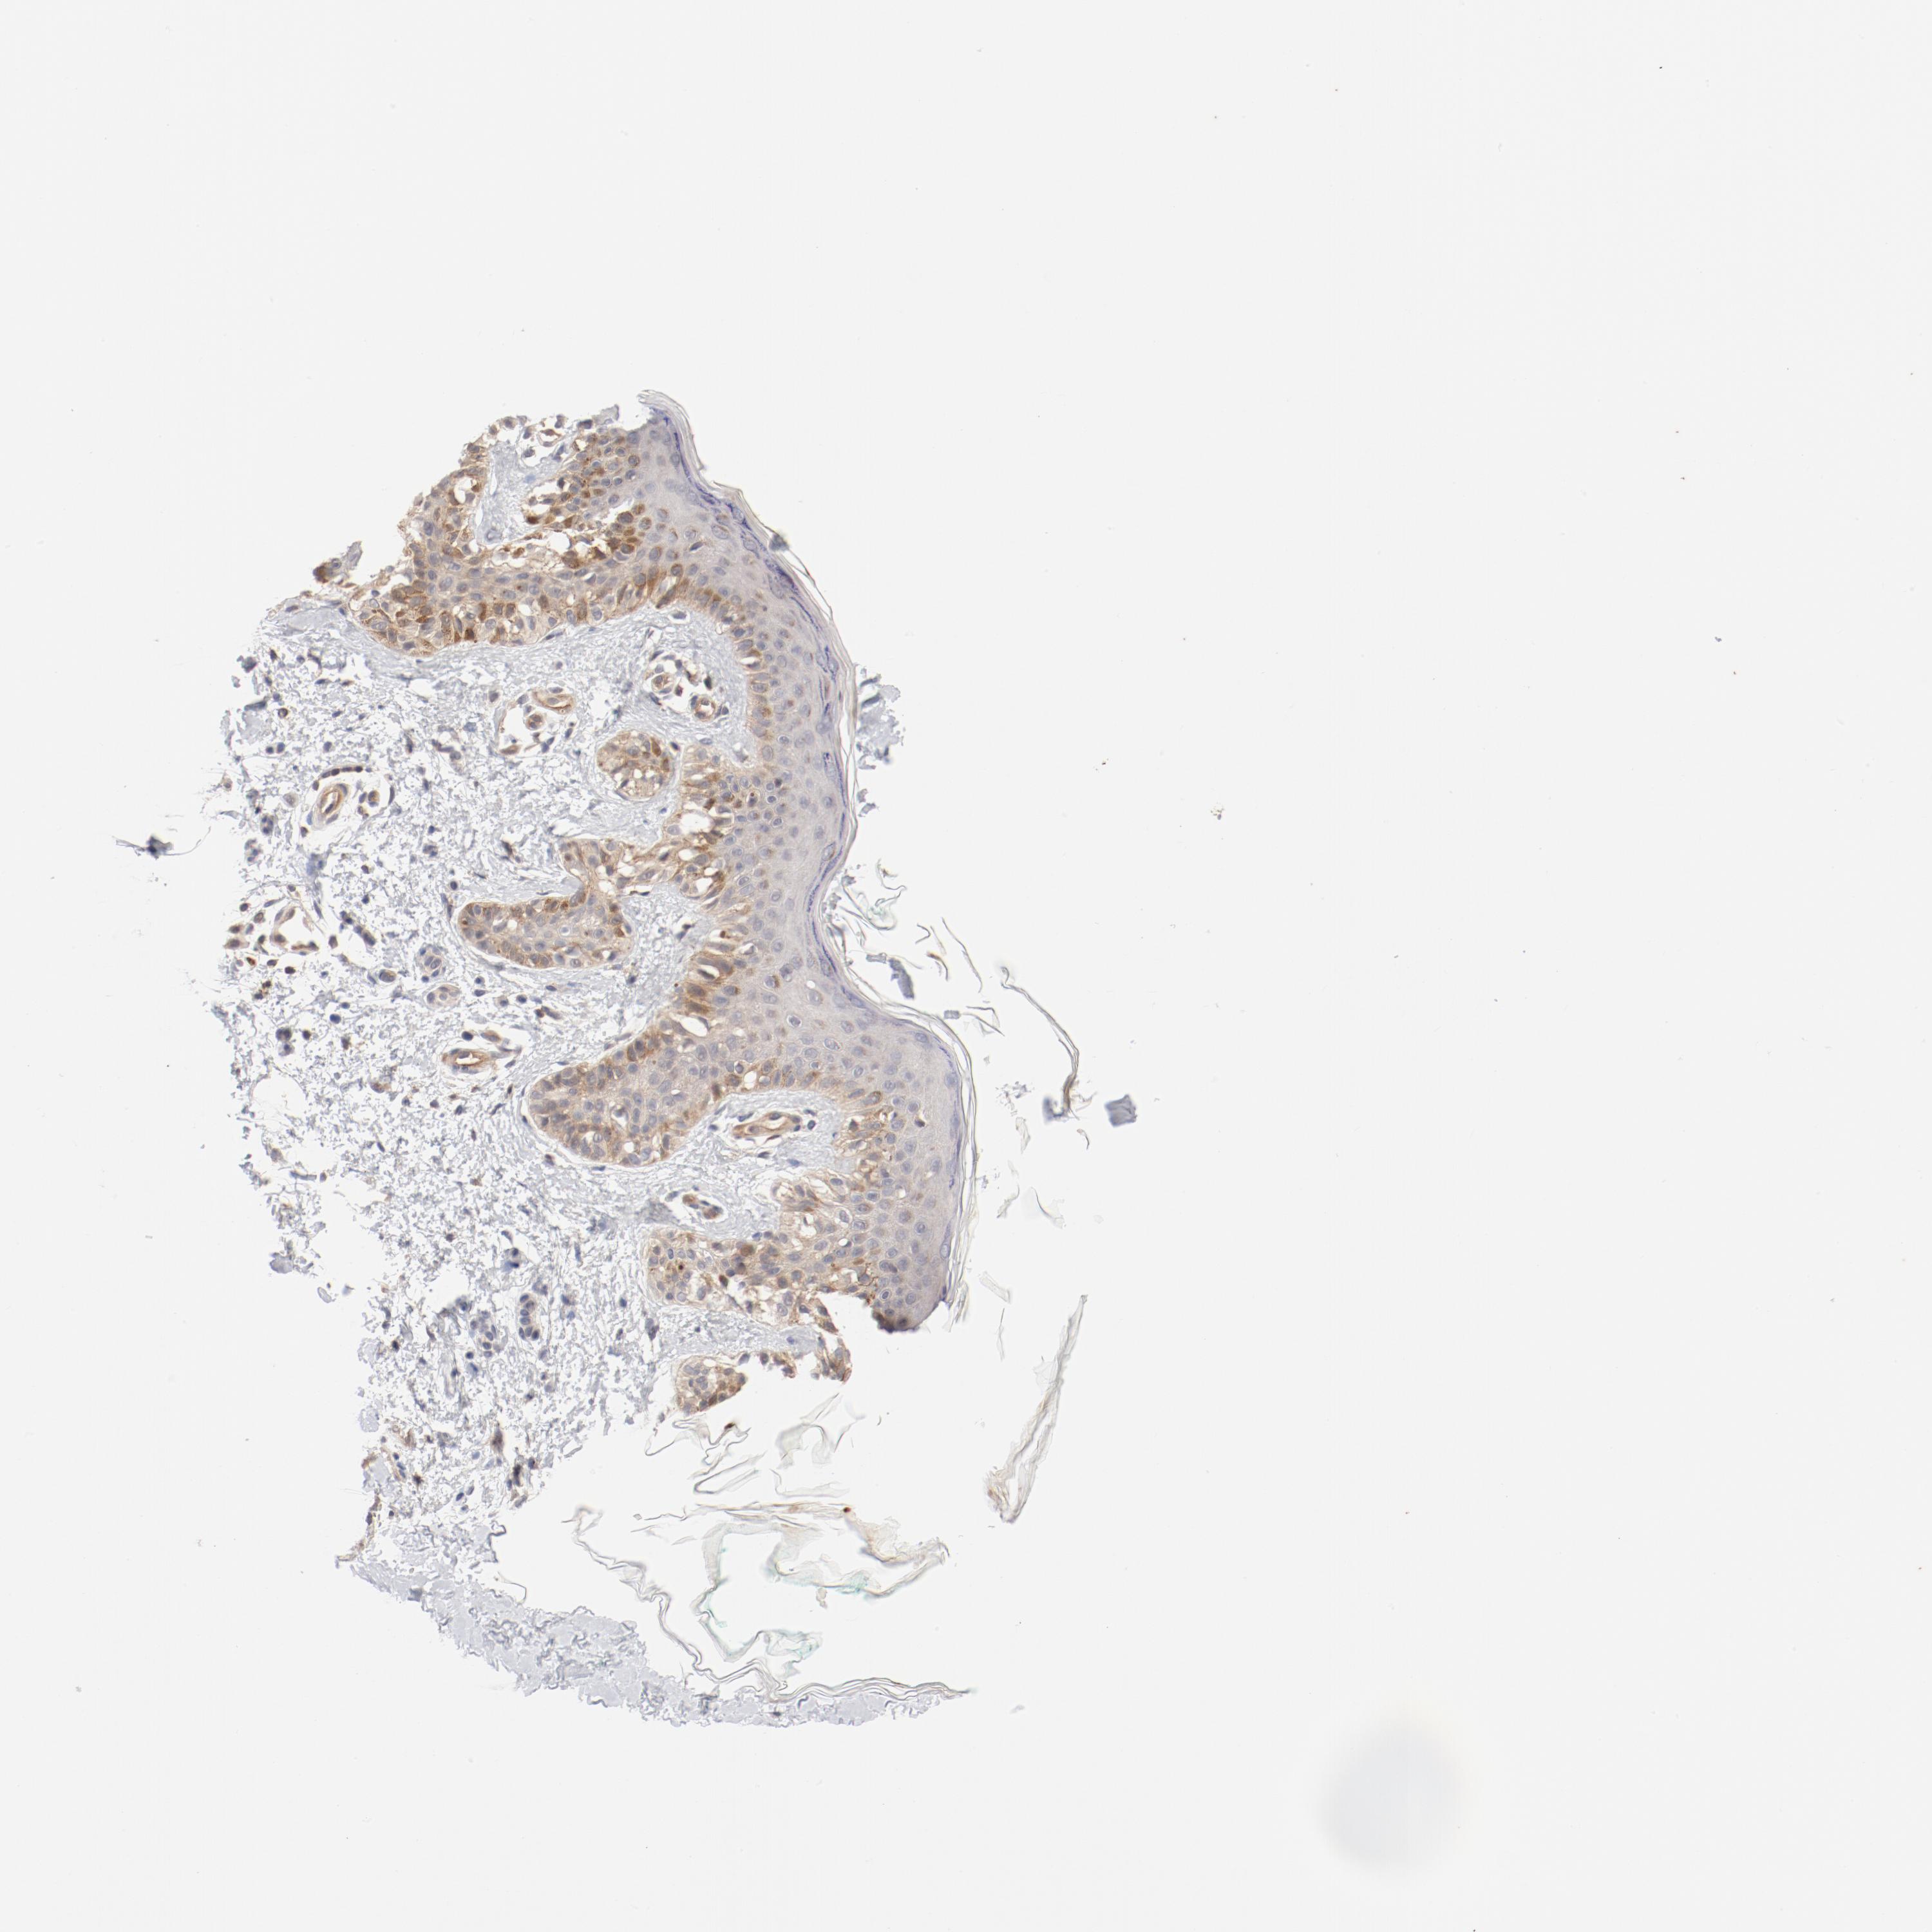

MELANOMA - Protein expressioni

A mouse-over function shows sample information and annotation data. Click on an image to view it in a full screen mode. Samples can be filtered based on level of antibody staining by selecting one or several of the following categories: high, medium, low and not detected. The assay and annotation is described here.

Note that samples used for immunohistochemistry by the Human Protein Atlas do not correspond to samples in the TCGA dataset.

Antibody stainingi

Antibody staining in the annotated cell types in the current human tissue is reported as not detected, low, medium, or high, based on conventional immunohistochemistry profiling in selected tissues. This score is based on the combination of the staining intensity and fraction of stained cells.

Each image is clickable and will lead to virtual microscopy that enables deeper exploration of all samples and also displays staining intensity scores, fraction scores and subcellular localization as well as patient and tissue information for each sample.

Antibody HPA003866

Staining

High

Medium

Low

Not detected

Intensity

Strong

Moderate

Weak

Negative

Quantity

>75%

75%-25%

<25%

None

Location

Nuclear

Cytoplasmic/membranous

Cytoplasmic/membranous,nuclear

Malignant melanoma, Metastatic site